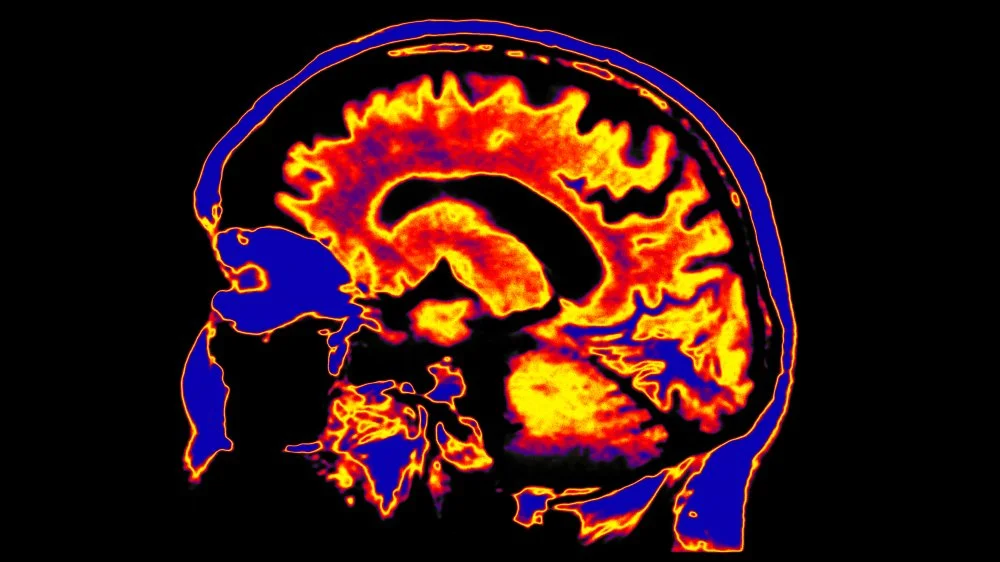

Les neuroscientifiques ont longtemps repéré plusieurs zones potentielles participant aux fonctions cognitives, mais l’identification d’un véritable « corrélat neural de la conscience » (NCC) est restée délicate. Cette étude montre, chez le macaque, que le thalamus central latéral constitue un candidat sérieux pour jouer ce rôle. Située au centre du prosencéphale, cette petite région semble pouvoir être stimulée pour contrebalancer l’effet d’agents dépresseurs de la conscience, comme l’anesthésie générale.

Les implications pratiques et théoriques sont multiples. Le professeur Earl Miller, du MIT, qualifie l’étude d’« importante » et souligne que les résultats renforcent l’hypothèse selon laquelle le thalamus central latéral aide à maintenir le cortex en état d’éveil (Gizmodo).